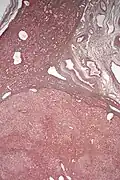

| Micrograph of a hepatic adenoma (bottom of image). H&E stain | |

Pathologic diagnosis

Hepatic adenomas are, typically, well-circumscribed nodules that consist of sheets of hepatocytes with a bubbly vacuolated cytoplasm. The hepatocytes are on a regular reticulin scaffold and less or equal to three cell thick.

The histologic diagnosis of hepatic adenomas can be aided by reticulin staining. In hepatic adenomas, the reticulin scaffold is preserved and hepatocytes do not form layers of four or more hepatocytes, as is seen in hepatocellular carcinoma.

Cells resemble normal hepatocytes and are traversed by blood vessels but lack portal tracts or central veins.

Inflammatory hepatocellular adenoma